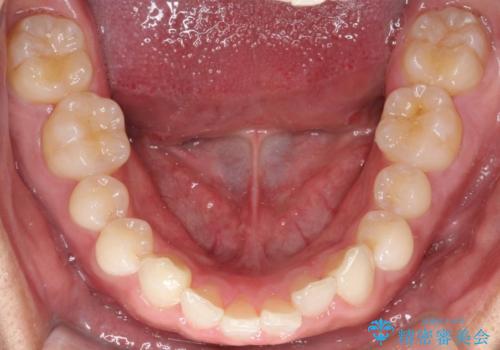

- 歯のデコボコと過蓋咬合を主訴に来院された患者様です。

アーチの拡大とIPRを行い非抜歯で治療を行いました。

歯を抜かずに叢生(デコボコ歯列)と過蓋咬合を改善する事が出来ました。